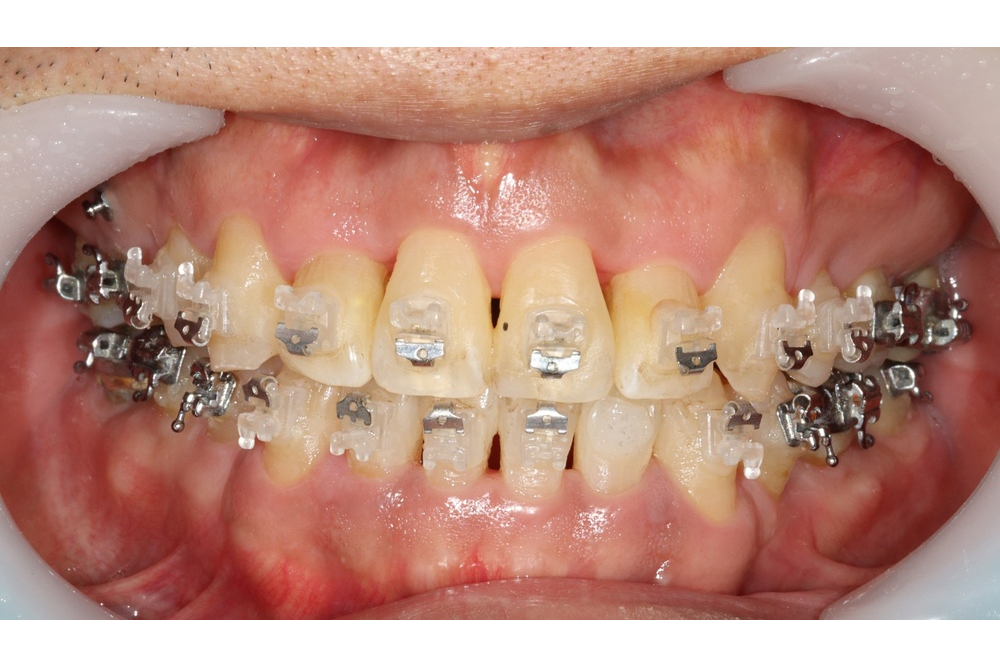

내려온 위 어금니를 올리는 김에, 앞니도 가지런하게 하기로 하고 장치를 붙여 배열하고 있습니다.

이를 끌어올리고 충치치료를 시행하였습니다.